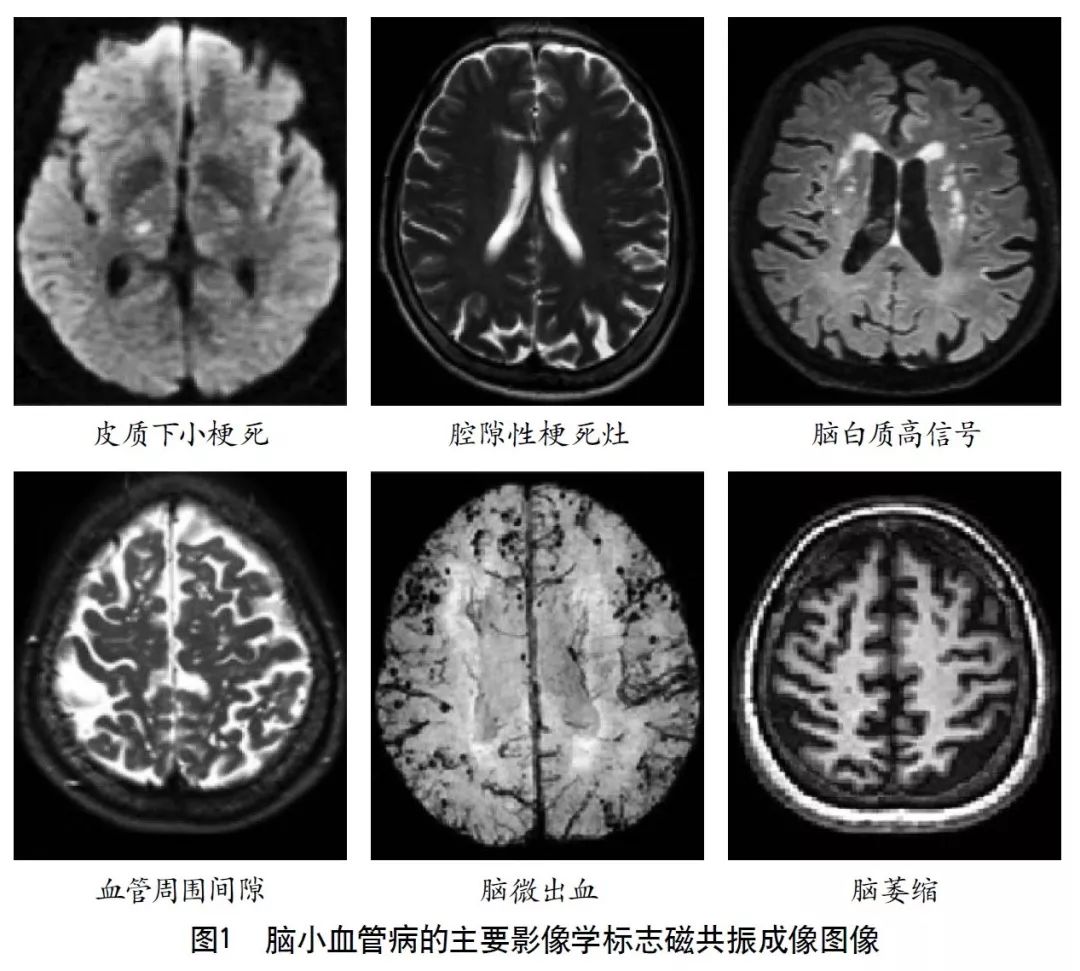

2011年,美国医学研究委员会、德国神经退行性疾病研究中心和加拿大卫生研究院共同建立了神经退行性疾病精英中心。2013年,该中心的核心专家组成员共同撰写了CSVD的共识指南,确立了代表CSVD的6种关键性损伤的神经影像学标志(图1),分别是近期皮质下小梗死、假定血管源性的腔梗灶、假定血管源性的白质高信号、PVS、脑微出血和脑萎缩。现将CSVD影像表现的相关影像技术介绍如下。

4.2.1 近期皮质下小梗死

根据2013年共识指南,近期皮质下小梗死的定义为:脑内一条穿支动脉供血区域的近期梗死,且伴有近期脑损伤一致的影像学特征或临床综合征表现。近期皮质下小梗死多发生在半卵圆中心、放射冠、基底节区、脑干等部位,MRI图像上呈T1WI低信号、T2WI高信号、FLAIR高信号、DWI高信号和GRE等信号。其轴位切面显示急性期梗死直径<20 mm,冠状位或矢状位可以>20 mm。

4.2.2 假定血管源性的腔隙灶

假定血管源性的腔梗灶定义为:圆形或卵圆形,直径为3~15 mm,分布于皮质下,充满与脑脊液相同信号,与穿支动脉供血区陈旧梗死或者出血相关。通常在FLAIR上表现为中心脑脊液样低信号,周边围绕环状高信号。但有时在FLAIR上也可表现为完全的高信号,在T1WI、T2WI上呈脑脊液样信号。

4.2.3 假定血管源性的白质高信号

假定血管源性的白质高信号定义为:脑白质异常信号,病变范围大小不等,在T2WI或FLAIR上表现为高信号,无腔隙,T1WI上呈等信号或低信号(不及脑脊液)。除非特别说明,皮质下灰质病变及脑干病变不属于白质高信号。假定血管源性的白质高信号的提出,排除了由其他非血管源性疾病所致的白质病变,如多发性硬化、白质营养不良等。

4.2.4 PVS

指南对PVS的定义为:穿过灰质或白质,与常见血管走行一致的充满液体的间隙。PVS扩张在MRI上主要表现为直径<3 mm的圆形、卵圆形或线形的,T1WI上低信号、T2WI上高信号(与脑脊液信号强度一致)、FLAIR上低信号、DWI上无弥散受限的病灶,通常边界清晰、无对比剂增强效应和占位效应。病灶形状取决于成像平面,成像平面与血管走行平行时呈线性,与血管走行垂直时呈圆形或卵圆形。该征象多见于基底节区靠近前联合附近、脑凸面皮层下、半卵圆中心、脑干及外囊,很少出现在小脑,常与假定血管源性的腔隙灶同时出现,需加以鉴别。普遍接受的用来区分两者的特点是PVS直径一般不超过3 mm,且在T2WI和FLAIR上不表现为围绕脑脊液样信号的环状高信号,除非间隙跨越白质高信号区。

4.2.5 脑微出血

脑微出血定义为在顺磁敏感的序列如T2加权梯度回波序列或SWI上表现为小的(通常直径为2~5 mm,有时达10 mm)散在低信号,对磁化效应敏感。病灶通常边界清楚、均质,在T2加权梯度回波序列上有高光溢出效应(指影像学上显示的微出血面积比实际含铁血红素沉积面积大)。需要鉴别的可能出现类似病灶的情况有铁和钙沉积、骨、正常血管断面的流空效应、弥漫性轴索损伤等。此外,还要区分小的陈旧性的深部自发性脑出血,其范围相比脑微出血更大,有不规则囊腔,且在T1WI上可见。常用的直观定量脑微出血的方法包括微出血解剖评分量表和观察者脑微出血评分量表。计算机自动分析是近年研究热点,它可以缩短评估时间,减少个体间评估差异。

4.2.6 脑萎缩

2013年的共识指南将脑萎缩定义为与特定的局灶性损伤,如脑外伤或脑梗死无关的脑容积减少。脑萎缩可以是广泛的或局部的(如特定的脑叶或海马等特定区域),可以是对称或不对称的,亦可以是组织选择性的(如发生在白质等某一特定组织层)。目前不同部位的脑萎缩有相应的诊断标准,全脑皮层萎缩分级用于评价全脑(图3);内侧颞叶萎缩分级主要评价颞叶内侧,重点是海马(图4);Koedam分级主要评价顶叶,尤其是扣带回和楔前叶(图5);Kipps/Davies分级主要评价额颞叶(图6)。推测脑组织减少是由脑沟(周围)和脑室(中心)的脑脊液空间相对于颅内容积扩大所引起的。